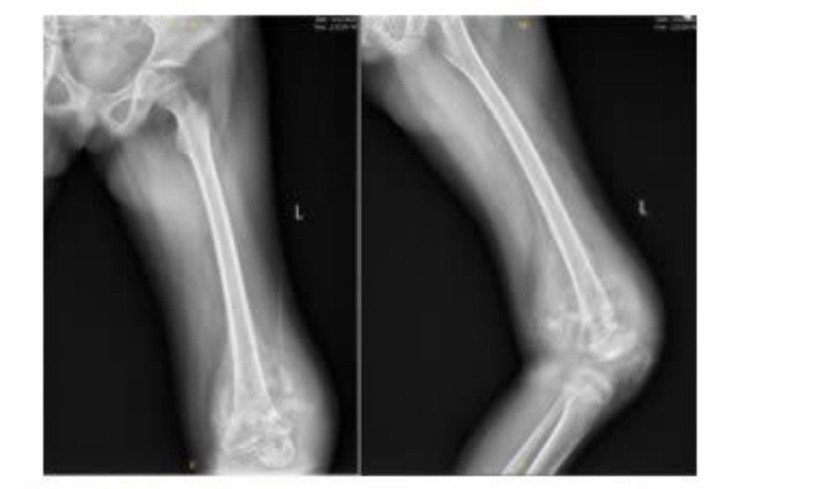

Bệnh nhi K.P.M., 10 tuổi, quê tại Điện Biên, người dân tộc Hà Nhì, nhập viện trong tình trạng sưng đau vùng đùi trái kéo dài, đi lại khó khăn. Qua thăm khám lâm sàng và thực hiện các xét nghiệm hình ảnh học, kết quả MRI cho thấy bệnh nhi M. có khối tổn thương kích thước 12x9cm ở đầu dưới xương đùi, ăn mòn vỏ xương, phá vỡ màng xương và lan vào phần mềm. Kết quả sinh thiết xác định bệnh nhi mắc osteosarcoma đầu dưới xương đùi trái– một thể ung thư xương ác tính thường gặp ở lứa tuổi thiếu niên.

Hình ảnh X Quang lúc bệnh nhi mới nhập viện. Ảnh: BVCC